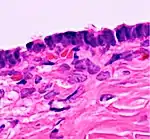

TypeSubtypeTypical microscopy findingsImage

CystadenomaSerous cystadenoma Cyst lining consisting of a simple epithelium, whose cells may be either:[21]

• columnar and tall and contain cilia, resembling normal tubal epithelium

• cuboidal and have no cilia, resembling ovarian surface epithelium